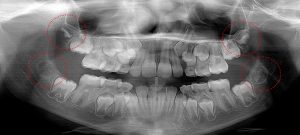

This 19 year old patient has all four 3rd molars present (circled). Only the upper left 3rd molar has fully erupted. The lower left 3rd molar is partially exposed and decaying while the lower right soft tissue impacted, both requiring extraction. Note the double crown on the upper right third molar.